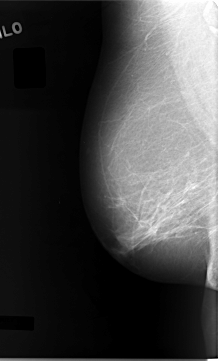

C_0027_1.RIGHT_CC

RIGHT_CC LINES 5888 PIXELS_PER_LINE 3808 BITS_PER_PIXEL 12 RESOLUTION 50 NON_OVERLAY